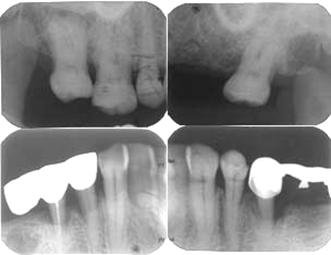

• X片示:25远中牙槽骨角形吸收至根尖,35-37远中牙槽骨角形吸收至根尖1/3区,45-44邻面牙槽骨角形吸收至根中1/2,17-16远中邻面牙槽骨水平吸收至根中1/2,上前牙牙槽骨水平吸收至颈1/3-中1/2

治疗前根尖片